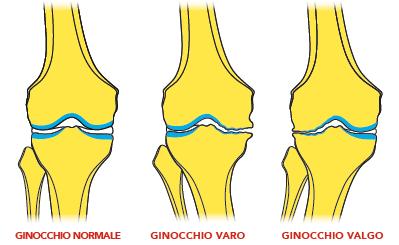

La valutazione ortopedica ha permesso di tipizzare il ginocchio da operare. Percorsi chirurgici specifici sono stati preparati per trattare pazienti affetti da artrosi primitiva o forme di artrosi secondaria. In ogni paziente è stata eseguita una pianificazione preoperatoria su radiografia panoramica per classificare il tipo di artrosi e il grado di deformità associata. La pianificazione clinica, valutando i difetti rotatori, l’allineamento femoro-rotuleo e la stabilità articolare, ha consentito la scelta del tipo di impianto e dell’approccio chirurgico.

Le ginocchia con gravi deviazioni assiali sono state trattate con protesi con inserti a stabilizzazione posteriore (a), semivincolate (b) o vincolate (c).